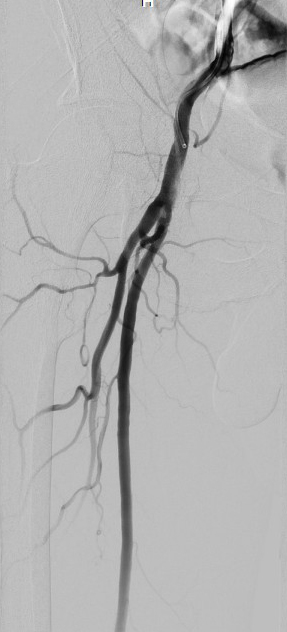

During the procedure, after sheath has been introduced, a local hematoma rapidly developed, which was treated by manual compression. Terminal aorta, common and external iliac arteries, and common femoral arteries had plaques and calcifications without significant stenosis. The angiogram showed right superficial femoral artery blood extravasation at the level of vascular access, an abnormal image that raise the suspicion of an extensive dissection (Figure 1), acute thrombotic occlusion of right popliteal artery and permeable left popliteal artery with calcified plaques (Figure 2), absent blood flow below the right knee and normal right calf arteries. Because the suspicion of an extensive dissection persisted, we removed the right femoral sheath and we achieved hemostasis by manual compression. We used a left femoral approach (5F) with cross over and the new images invalidate the diagnosis of superficial femoral artery dissection (Figure 3) and confirm the acute thrombotic occlusion of right popliteal artery (Figure 4).

Figure 3. Angiogram of the right fe­moral artery after cross over from the left femoral artery. There are no signs of dissection.